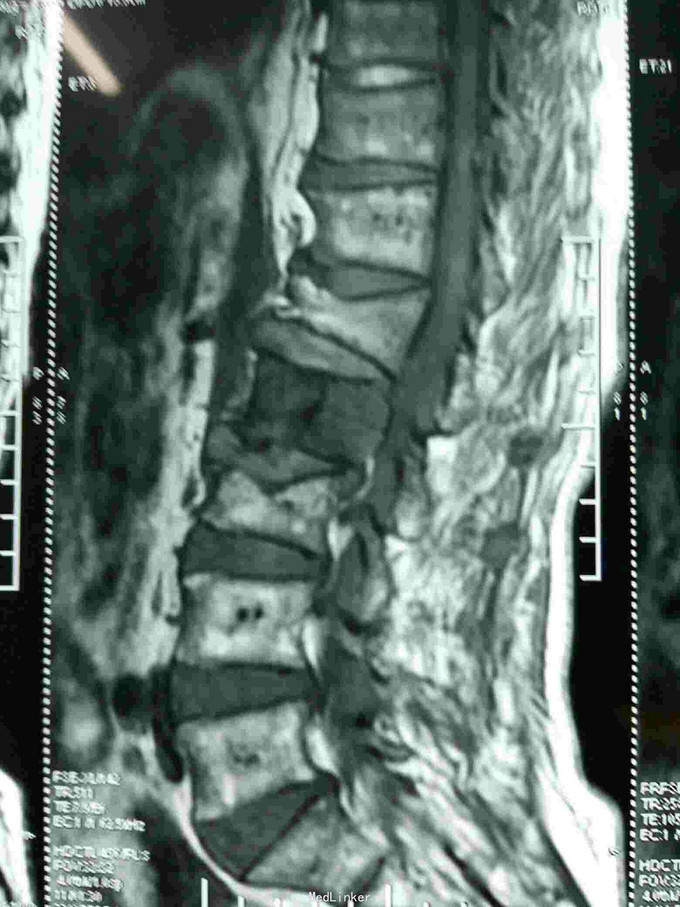

根据病史查体诊断:腰间盘突出症待确诊。应用消肿营养神经镇痛治疗。一天。查核磁共振示:腰椎多节段间盘突出伴椎管狭窄。第二腰椎骨破坏侵及椎板。部分突入椎管,脊髓受压。诊断:腰间盘突出伴椎管狭窄。第二腰椎转移癌,脊髓受压。经与家属沟通,查双肺CT:双肺下叶炎症。肺部纤维化。可见肿瘤阴影。肋骨及胸膜受累。胸椎部分骨破坏。最终诊断:双肺癌,胸椎,腰椎骨转移,脊髓受压。多节段腰椎间盘突出。病人至肿瘤科治疗。